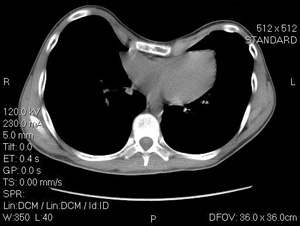

A CT scan of a 14 year old male with severe pectus excavatumIn addition to its more serious symptoms, pectus excavatum may have negative psychosocial effects in children and teenagers, who often experience self-consciousness and difficult peer interactions stemming from their appearance. Often activities that expose the chest are avoided.

• CT-scan

• Haller Index: A measure of the extent of pectus excavatum by means of the CT scan. It is calculated by obtaining the ratio of the horizontal distance of the inside of the ribcage and the shortest distance between the vertebrae and sternum. A Haller Index of greater than 3.25 is generally considered severe (a normal Haller Index is 2.5).